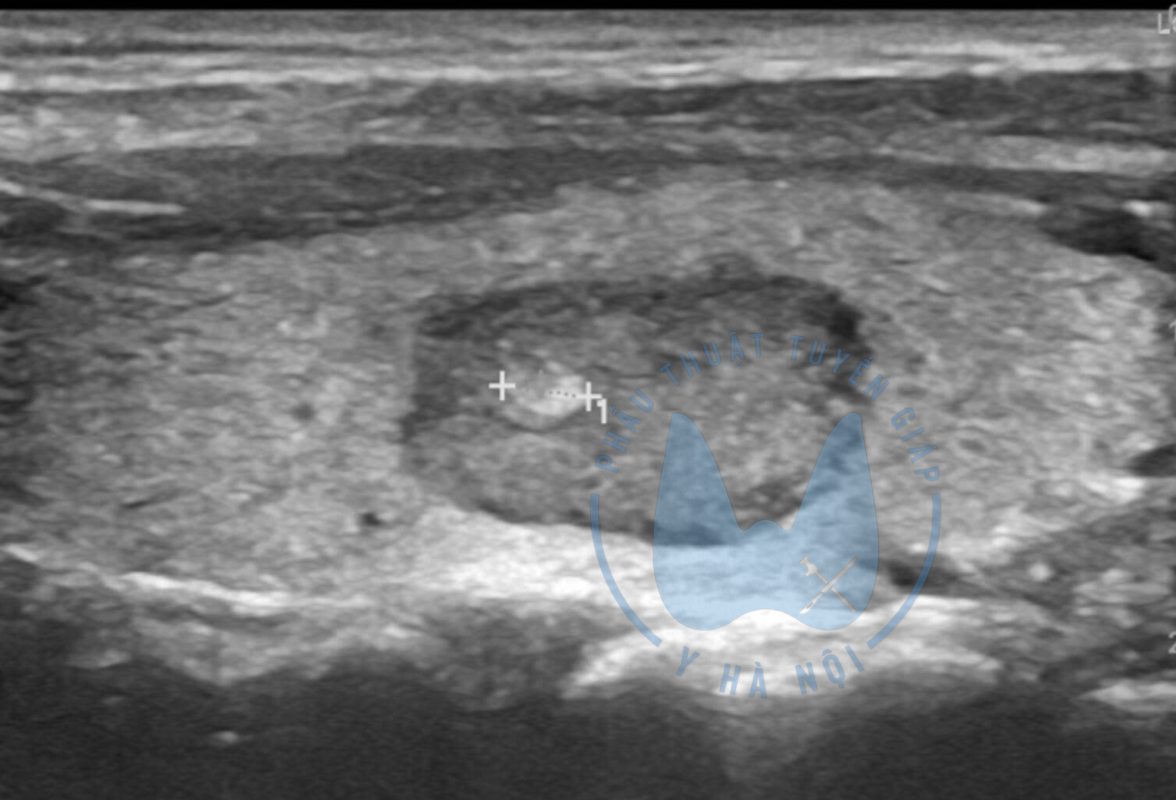

Phẫu thuật tuyến giáp hiện nay đóng vai trò quan trọng trong điều trị khá nhiều bệnh lý tuyến giáp như: ung thư tuyến giáp, bướu lành tuyến giáp, bệnh basedow, bướu nhân độc tuyến giáp… Phẫu thuật có thể bao gồm

- Phẫu thuật nội soi điều trị u tuyến giáp tái phát sau đốt sóng cao tần có an toàn hay không?

- Điều trị u tuyến giáp lành tính hiệu quả

- Ung thư tuyến giáp di căn hạch có cần thiết cắt toàn bộ tuyến giáp hay không?